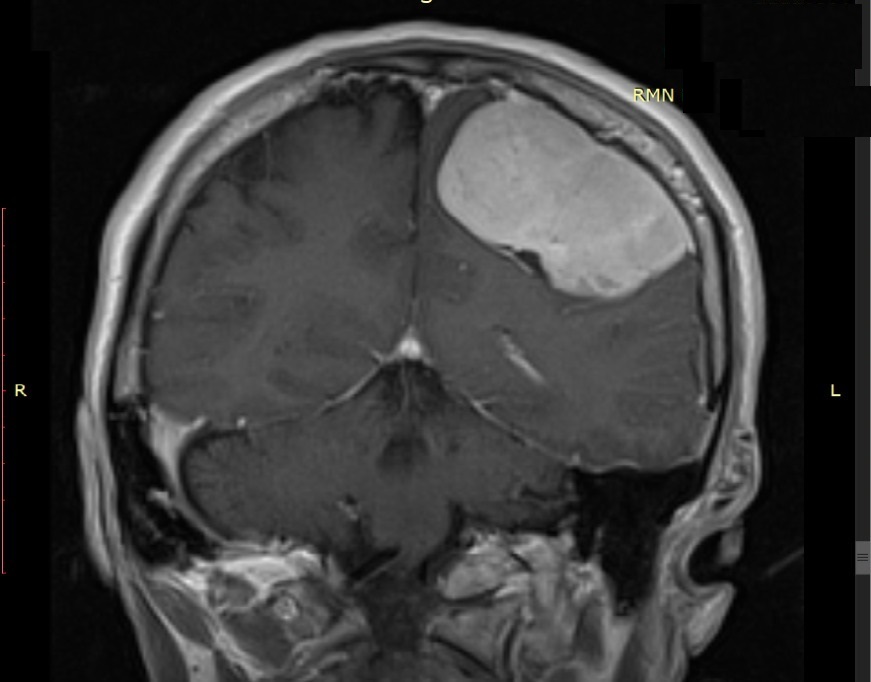

„Pacientul a fost internat ieri prin Unitatea de Primiri Urgențe, fiind diagnosticat cu o tumoră cerebrală gigantă care îi punea viața în pericol, prin comprimarea creierului. I s-au efectuat analize medicale, inclusiv testul pentru COVID-19. După studierea atentă a cazului am decis intervenția chirurgicală și am practicat rezecția completă a tumorii care a avut o mărime de 6/5 cm”, explică Șef Lucrări Dr. Vicențiu Săceleanu.

Intervenția chirurgicală a fost efectuată cu microscopul operator performant din dotarea secției și a durat aproximativ 4 ore. Operația a fost un succes și urmează ca pacientul să fie suspus unor controale post operatorii amănunțite.